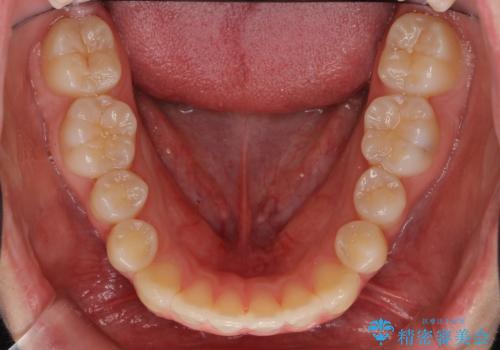

前歯のがたつき 乳歯を抜かずに矯正

- 前歯のがたつきを主訴に来院。

右上に乳歯が残っていましたが、後継永久歯がないため、抜かずに矯正しました。

乳歯の部分が反対咬合でしたが、歯列矯正で被蓋が改善するように移動させました。

右上の乳歯は移動させましたが、幸い矯正後にぐらつくこともなく、そのまま抜けるまで使うことにしました。